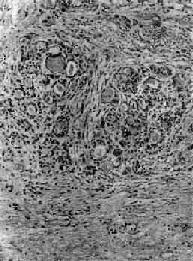

肉眼观,甲状腺对称性弥漫肿大,一般为正常的2~4倍,质较软,切面灰红,胶质含量少。镜下,以滤泡增生为主要特征,滤泡大小不等,以小型滤泡为主。小型滤泡上皮呈立方形,大型滤泡上皮多为高柱状,常向腔内形成乳头状突起。滤泡腔内胶质少而稀薄,胶质的周边部即靠近上皮处出现大小不等的空泡,有的滤泡内甚至不见胶质。间质中血管丰富,显著充血,有多量淋巴细胞浸润并有淋巴滤泡形成(图15-7)。经碘治疗的病例,由于碘能阻断含甲状腺素胶质的分解和促进胶质的储存,故胶质增多变浓,上皮增生受抑制,间质充血减轻,淋巴细胞也减少。与此相反,经硫脲嘧啶等阻断甲状腺素合成的药物治疗者,由于血中TSH代偿性增加,故滤泡增生更明显,上皮呈高柱状,胶质更稀少甚至消失。

图15-7 毒性甲状腺肿

滤泡增生,有的扩大,上皮呈立方或高柱状,并乳头状突起。滤泡腔内胶质稀薄,周边有大小不等空泡